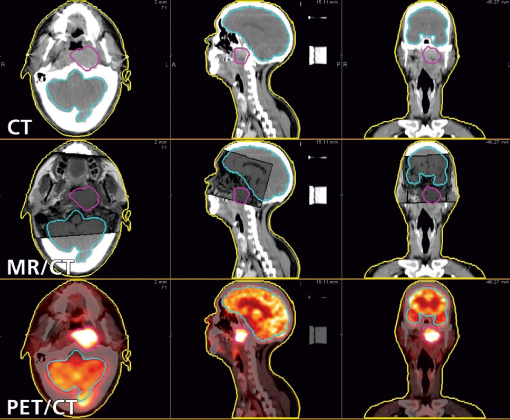

Deforme Edilebilir MR/CT | Sonuçların Doğruluğu Güvence Altındadır!

Çoklu modaliteli deforme edilebilir hizalama, çözmesi zor bir problemdir. Reg Reveal aracı icat edilmeden önce daha da zor bir iş, hizalamanın doğru olup olmadığını saptamaktı. Günümüzde Reg Reveal ve Reg Refine sayesinde MIM, CT deforme edilebilir hizalamayı planlarken MR’ın doğruluğundan emin olabilirsiniz.

Deforme Edilebilir PET/CT | En İyi PET Hedef Hacim Konturlama

İlk PET/CT hizalama işleminden GTV’lerin konturlanmasına kadar tüm işlerde MIM Maestro, PET görüntülerini tedavi planlama CT’leriyle birleştirmek için bir çözüm sunmaktadır. MIM için üretilen PET Edge™ aracı, PET ağır lezyonları doğru ve istikrarlı konturlamaktadır.

PET Edge, gradiyene dayalı bir tekniktir. PET aktivitesindeki en dik inişi saptayarak kontur sınırını otomatik oluşturur ve genel eşik tekniğine kıyasla istatistik açısından daha doğru olmasını sağlar. Bu araç, görsel kontrast ne olursa olsun PET görüntüleri üzerine tümör hacimlerini çizerken istikrarlı sonuçlar elde edilmesini sağlar.